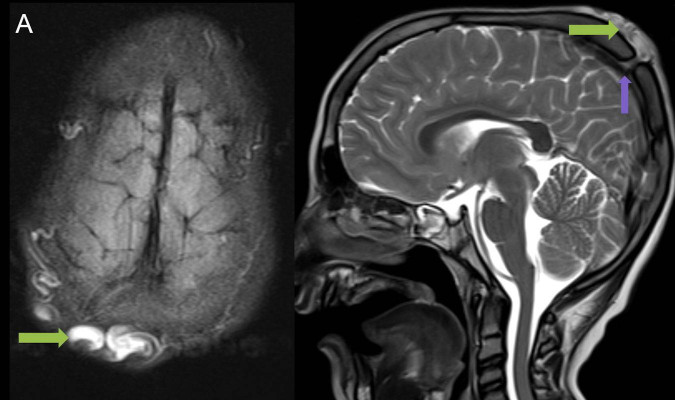

1. A) Kontrastlı FLAIR aksiyel görüntüde ve sagital T2A görüntüde vertekste orta hatta cilt altında dilate tortiyoze vasküler kollateraller (oklar). Paryetal kemikte orta hatta defekt (ok) ve defekt ile ilişkili vasküler yapıların cilt altı yumuşak dokulara uzanımı izlenmektedir.